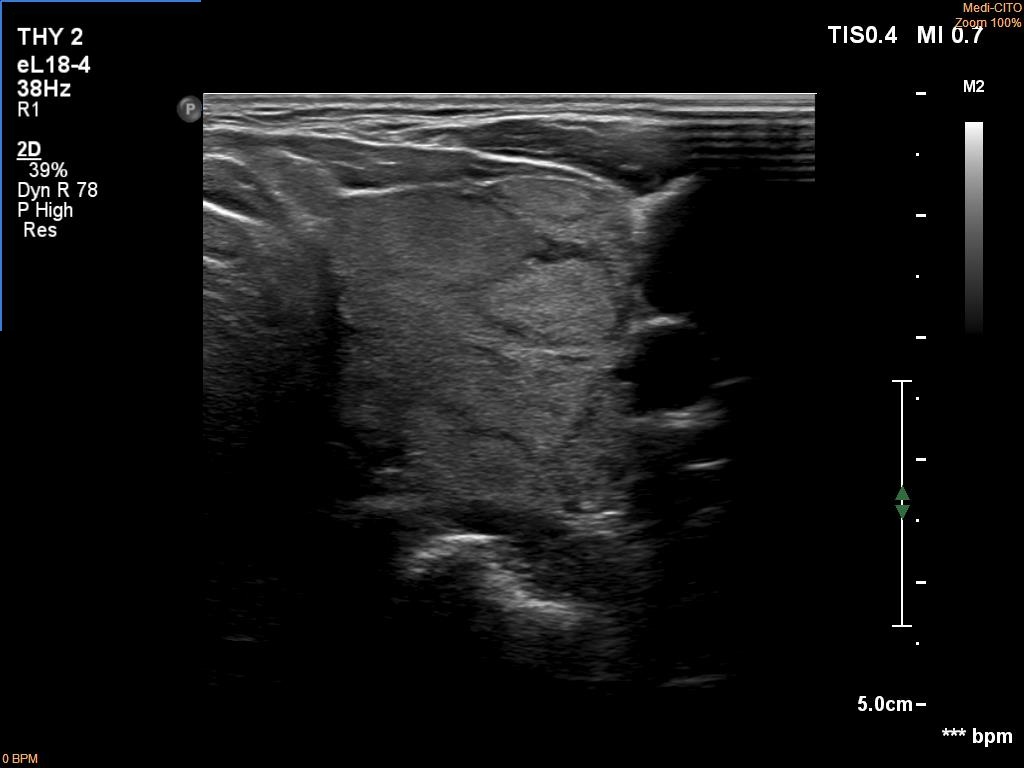

First examination (first row of images):

Clinical data: A 75-year-old woman was referred for evaluation of a goiter which was palpated by her GP.

Palpation: Both lobes were a bit firm and enlarged. There was a firm nodule in the isthmus.

Laboratory tests: TSH 4.49 mIU/L, aTPO 40 U/mL.

Ultrasonography. The thyroid was echonormal and had numerous discrete echonormal lesions. The largest of them was located in the isthmus. None of the lesions shared oncological importance.

Cytology was performed form the lesion in the isthmus and resulted in lymphocytic thyroiditis.

Suggestion: TSH and ultrasound in a year.